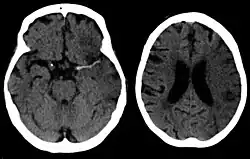

Silent stroke

Silent stroke is stroke that does not have any outward symptoms, and people are typically unaware they had experienced stroke. Despite not causing identifiable symptoms, silent stroke still damages the brain and places the person at increased risk for both transient ischemic attack and major stroke in the future. Conversely, those who have had major stroke are also at risk of having silent stroke.[62] In a broad study in 1998, more than 11 million people were estimated to have experienced stroke in the United States. Approximately 770,000 of these were symptomatic and 11 million were first-ever silent MRI infarcts or hemorrhages. Silent stroke typically causes lesions which are detected via the use of neuroimaging such as MRI. Silent stroke is estimated to occur at five times the rate of symptomatic stroke.[63][64] The risk of silent stroke increases with age, but they may also affect younger adults and children, especially those with acute anemia.[63][65]

Imaging

For diagnosing ischemic (blockage) stroke in the emergency setting:[77]

- CT scans (without contrast enhancements)

- sensitivity= 16% (less than 10% within first 3 hours of symptom onset)

- specificity= 96%

- MRI scan

- sensitivity= 83%

- specificity= 98%

For diagnosing hemorrhagic stroke in the emergency setting:

- sensitivity= 89%

- specificity= 100%

- sensitivity= 81%

For detecting chronic hemorrhages, an MRI scan is more sensitive.[78]

CT scans may not detect ischemic stroke, especially if it is small, of recent onset,[10] or in the brainstem or cerebellum areas (posterior circulation infarct). MRI is better at detecting a posterior circulation infarct with diffusion-weighted imaging.[79] A CT scan is used more to rule out certain stroke mimics and detect bleeding.[10] The presence of leptomeningeal collateral circulation in the brain is associated with better clinical outcomes after recanalization treatment.[80] Cerebrovascular reserve capacity is another factor that affects stroke outcome – it is the amount of increase in cerebral blood flow after a purposeful stimulation of blood flow by the physician, such as by giving inhaled carbon dioxide or intravenous acetazolamide. The increase in blood flow can be measured by PET scan or transcranial doppler sonography.[81] However, in people with obstruction of the internal carotid artery of one side, the presence of leptomeningeal collateral circulation is associated with reduced cerebral reserve capacity.[82]